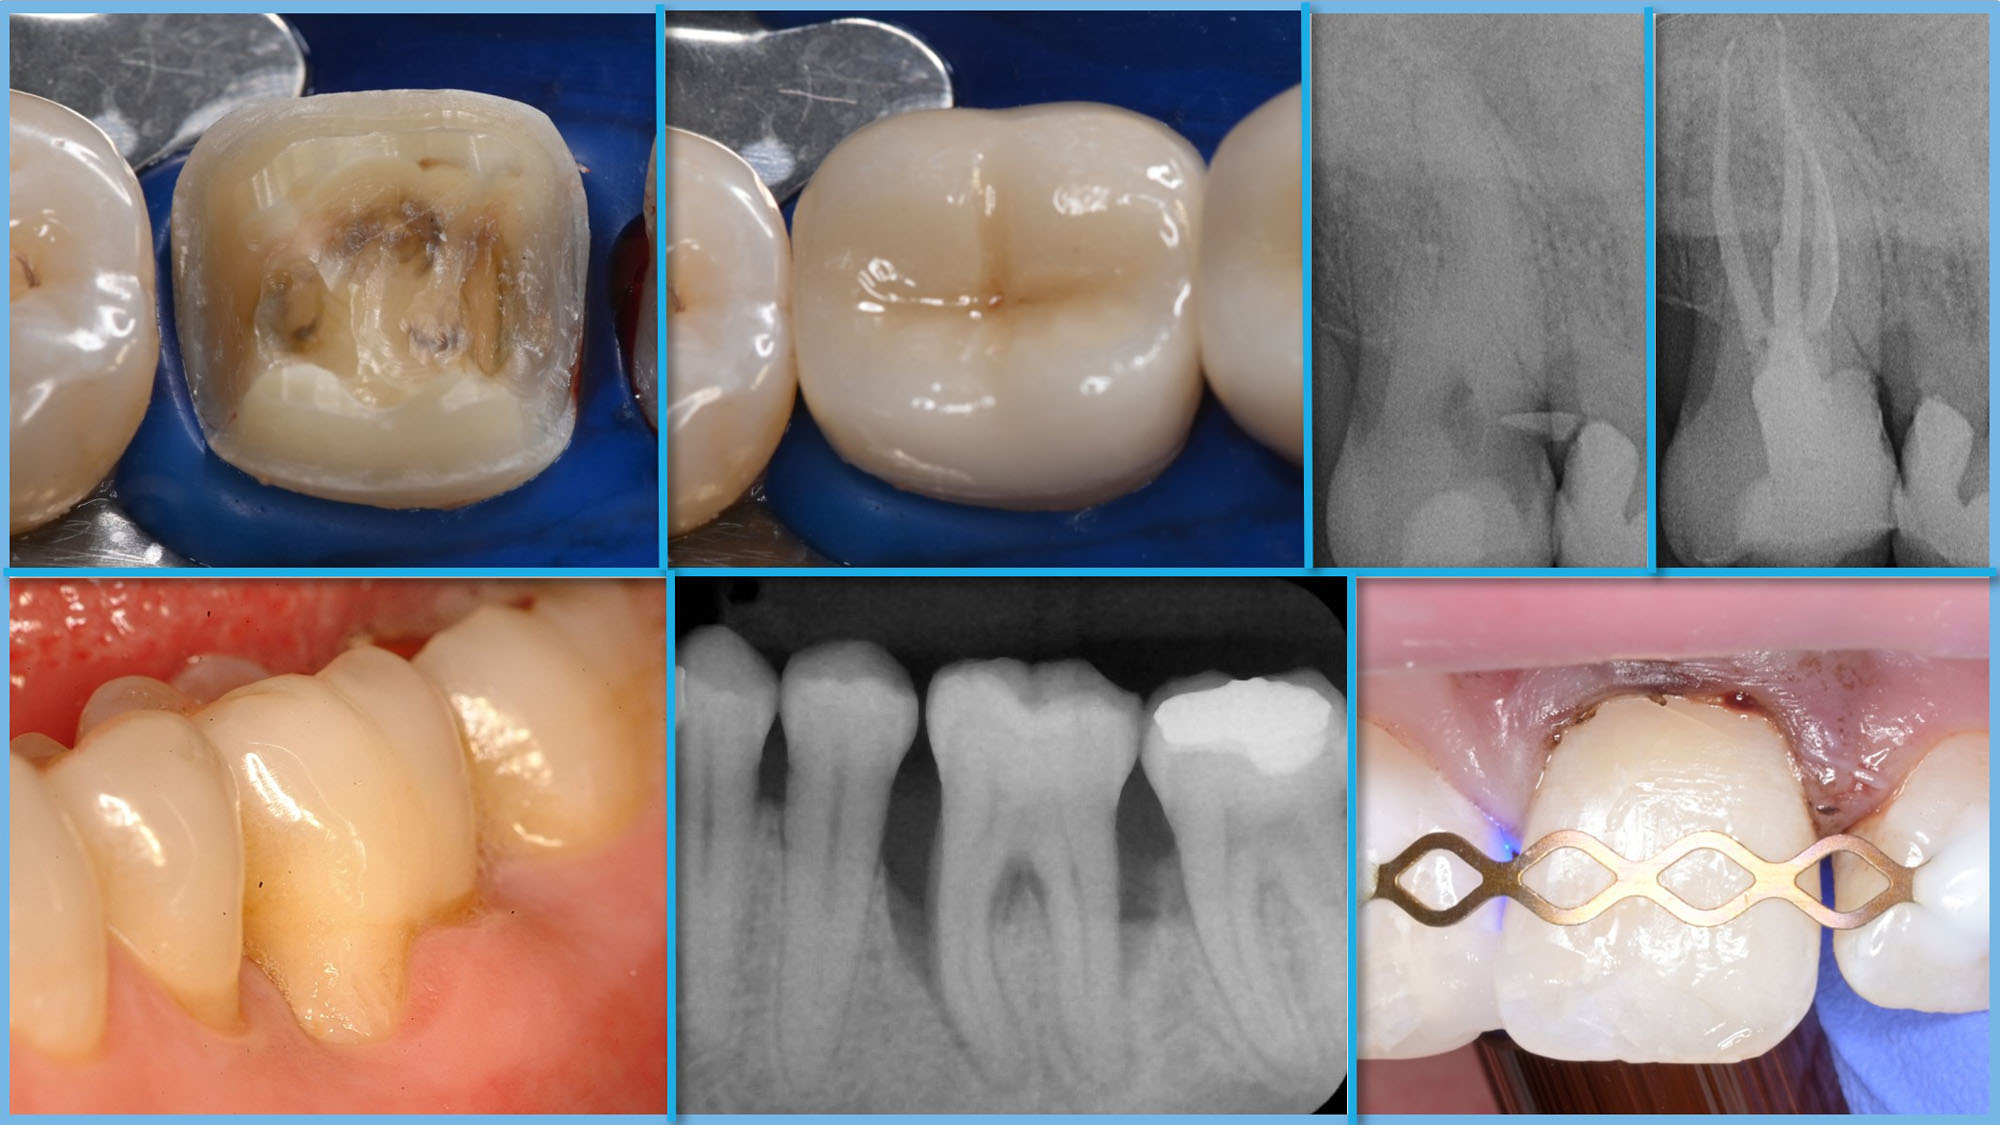

Dental Conservation (M.Sc.)

Conservative Dentistry, Periodontology, Endodontology, Pediatric Dentistry

Degree Master of Science

Start of degree program Winter semester

Admission Qualification assessment

Area of study Dentistry